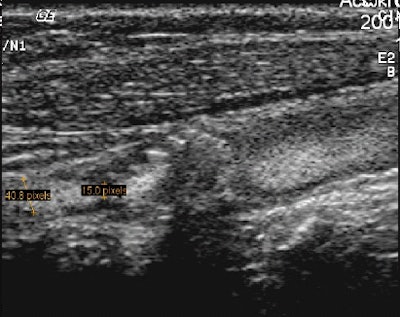

![]() |

| The researchers measured stenosis on both static and video-loop B-flow images. Image courtesy of Dr. Brian Garra. |